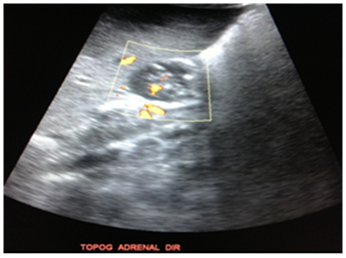

Abdominal CT scan demonstrates multiple rounded formations, predominantly hypodense, well delineated, showing heterogeneous impregnation after the infusion of intravenous contrast, especially one in the right hepatic lobe measuring approximately 11.0x8.3x6.4cm. It was also noted left perihilar para-aortic lymphadenopathy and interaortocaval lymphadenopathy with a confluent aspect and an expansive formation, ovoid, heterogeneous, predominantly hypodense with calcifications inside, measuring about 3.7x2.2 cm in its major axis in the right adrenal (Figures 4A) (Figure 4B).

Figure 4 In A, an abdominal CT-scan in axial section without contrast demonstrates multiple rounded formations, predominantly hypodense, especially one in the right hepatic lobe. In B, abdominal CT-scan in axial section with venous contrast demonstrates left perihilar para-aortic and interaortocaval lymphadenopathy with a confluent aspect and an expansive formation, heterogeneous with contrast enhancement.